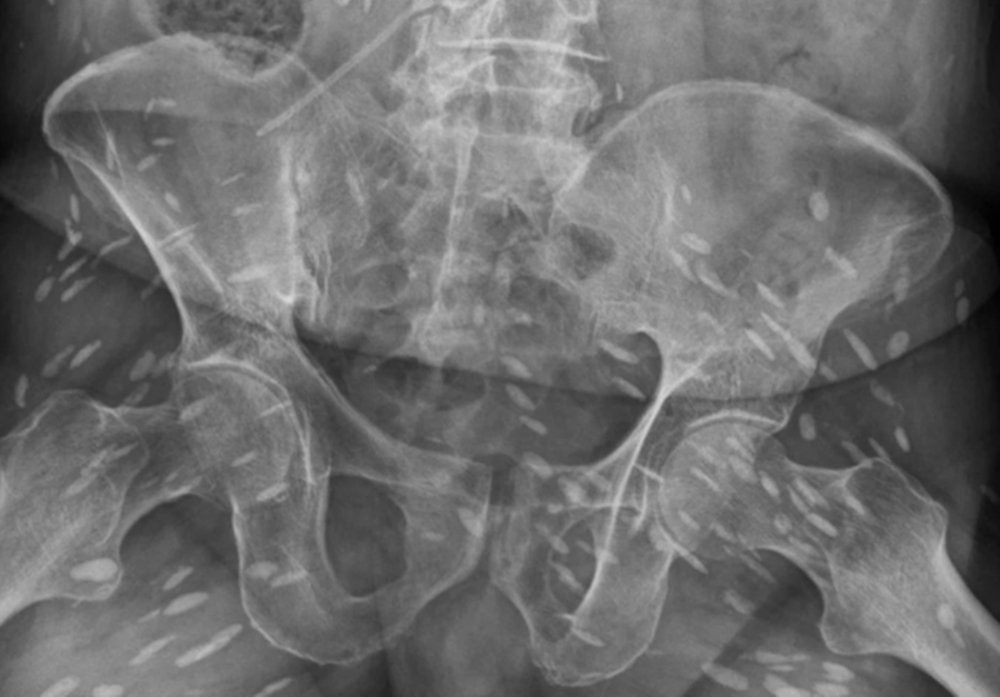

Hình ảnh phim chụp cho thấy chi chít trứng sán trong cơ thể người đàn ông 74 tuổi ở Đài Loan. (Ảnh: The Sun)

Tại đây, qua phim chụp CT, MRI và X-quang, các bác sĩ thấy hình ảnh chi chít trứng sán trong não, cột sống, cổ, ngực và chân tay bệnh nhân. Đây cũng chính là nguyên nhân khiến não bệnh nhân bị ảnh hưởng, gây ra tình trạng mất trí nhớ và không thể đi lại.